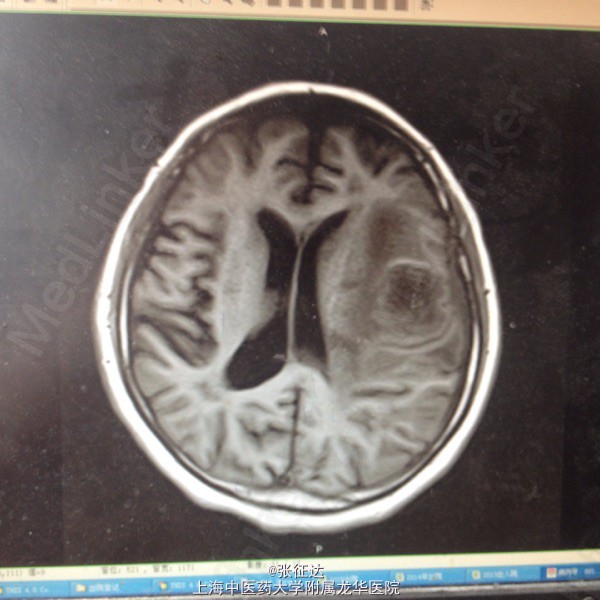

神情,GCS14分,右侧肢体肌力III级,病理症(-)。头颅CT:左侧顶叶区占位

复查头颅MR表现为左侧顶叶占位。择期全麻下行手术治疗后取病理,提示脑脓肿